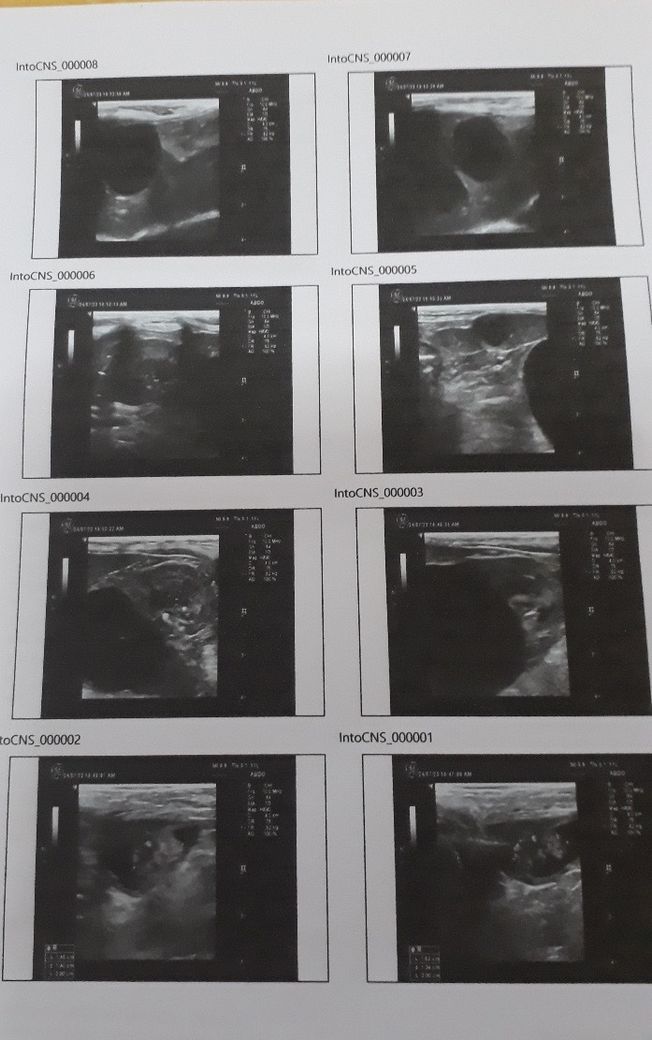

초음파만 해도 종양 양성,악성 알 수 있을까요?

10살 강아지 건강검진 했는데요 간,신장,비장에 종양이 있다고 합니다.ㅠㅠ

초음파만으로 악성, 양성을 구분할 수 없고, 악성 양성을 구분하고 어떤 종양인지 파악하기 위해서는 조직검사가 최종 답안지입니다. 통상 간, 비장, 신장에 종괴성 병변이 동시에 존재하면 혈관육종의 가능성을 높게 두고 가정해야 하니 주치의와 잘 협의하시고 빠른 시간내에 조직검사를 받아 보시는걸 추천합니다.